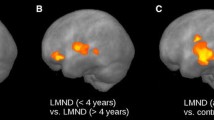

Longitudinal voxelwise differences of TDP-43G298S mice were compared to longitudinal voxelwise differences of wt mice. ΔFA was linearly normalized to an identical time-interval prior to statistical comparison. The WBSS of ΔFA for TDP-43G298S vs wt mice not only confirmed the loss of FA in the M1/M2 cluster, but also demonstrated an additional cluster in the agranular insular cortex (Fig. 2, Table 1).

Whole brain-based spatial statistics (WBSS) for the comparison of FA values and for the comparison of ΔFA. Cross-sectional comparisons were performed for TDP-43G298S mice vs wt at baseline and at follow-up and for TDP-43G298S mice follow-up data vs baseline data; longitudinal comparison (ΔFA) was performed for TDP-43G298S mice vs wt. Left panel: projectional views. Right panel: slicewise presentation of results clusters. Hot colors indicate an FA reduction or an increased ΔFA, respectively. M1, M2 – motor area 1,2, p. thal. n. – posterior thalamic nucleus, cing. Cortex – cingulate cortex, retrosp. Gran. Cortex – retrosplenial granular cortex, agran. Ins. cortex – agranular insular cortex